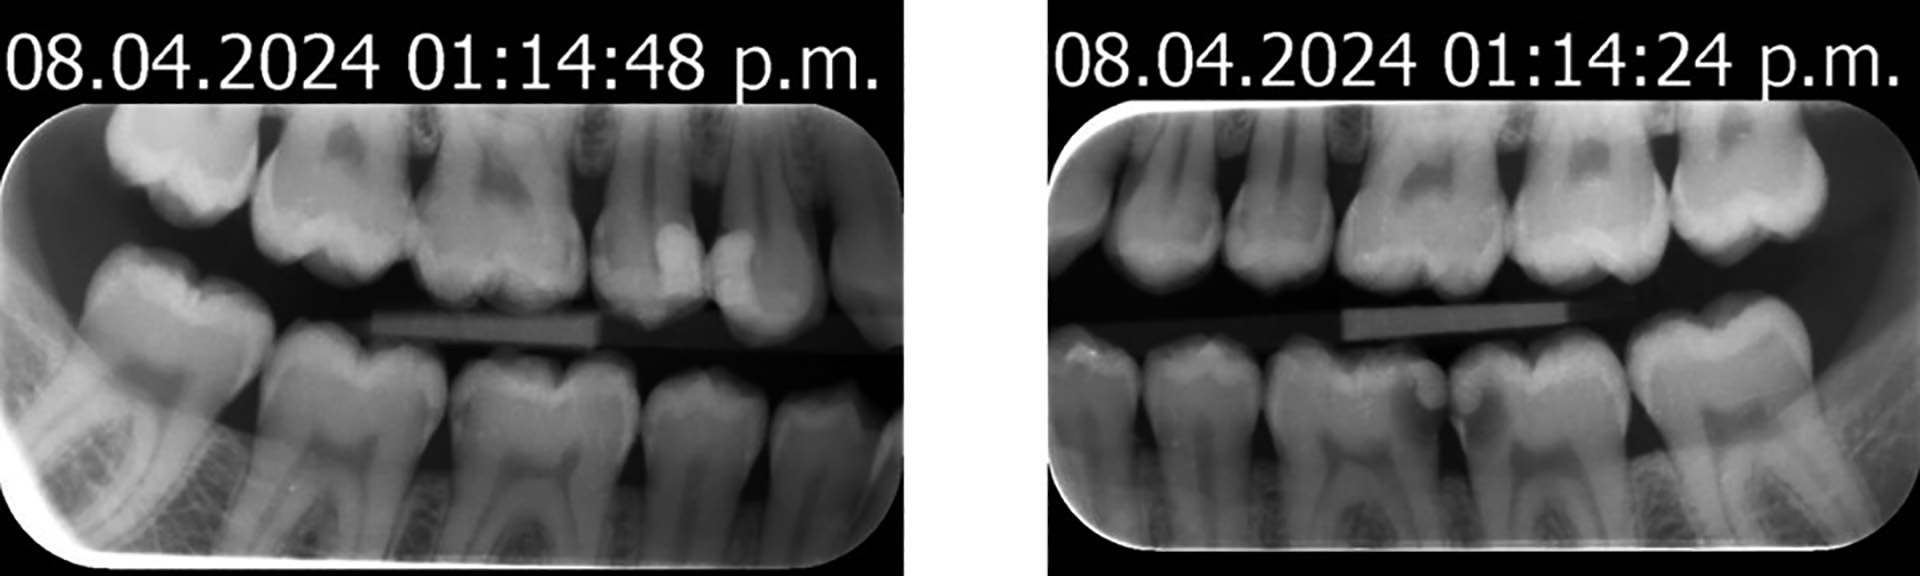

Pasienten hadde nylig vært hos sin nye tannlege, tannlege A, hvor det ble gjennomført en standard klinisk undersøkelse med rens og to bitewing-røntgenbilder, etterfulgt av en behandlingsplan. Da planen var svært omfattende, ønsket pasienten en uavhengig vurdering. Pasienten fikk anbefalt tannlege B av en arbeidskollega og tok kontakt med denne via e-post for en ny vurdering (second-opinion). Vedlagt i e-posten forelå en kopi av behandlingsplanen fra tannlege A (tabell 1). Det ble også innhentet røntgenbilder fra tannlege A (figur 1, 08.04.2024), og time for ny vurdering ble gitt. Basert på denne bakenforliggende informasjonen synes tannlege B at omfanget av tannlege A sin behandlingsplan er for stort. Tannlege B ønsker derfor etter tillatelse fra pasienten om å rådføre seg med en universitetstilknyttet kariolog (A.M).

Figur 1. Røntgenbilder tatt hos tannlege A, tilsendt tannlege B via e-post i forkant av en fornyet vurdering. Bilder publiseres med samtykke fra pasient og tannlegene A og B.